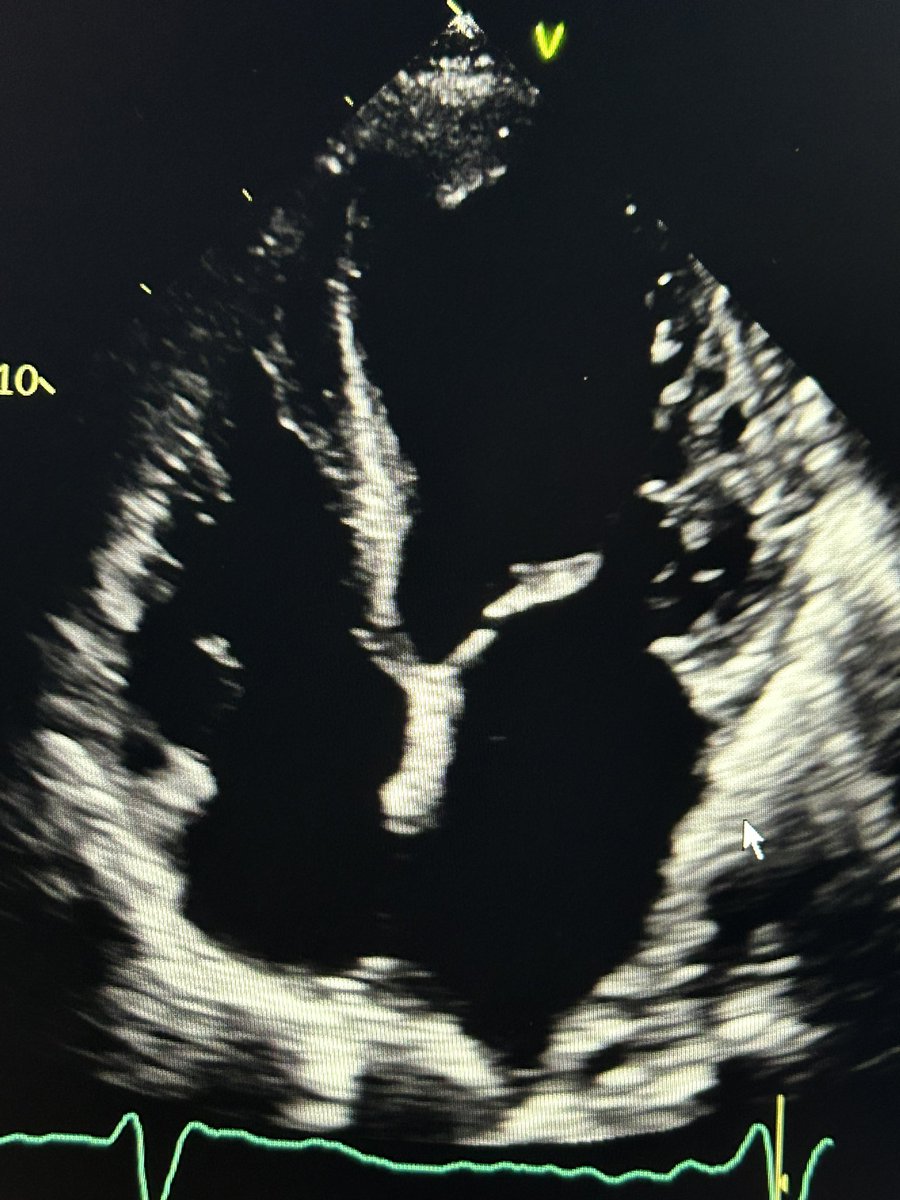

Well here is a rib space lower - from the still image you can already appreciate that the LV is more elongated. So now the previous image definitely looks foreshortened compared to this window… what about it moving?

Now in the one clip you appreciate the septum and apex are thinned and akinetic. Great environment for thrombus to hang out … oh what’s that flicking towards the apex?!

We would have missed that from the first foreshortened window wouldn’t we?